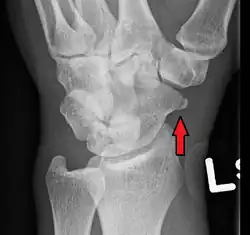

Fracture of the tubercle of the scaphoid bone of the wrist